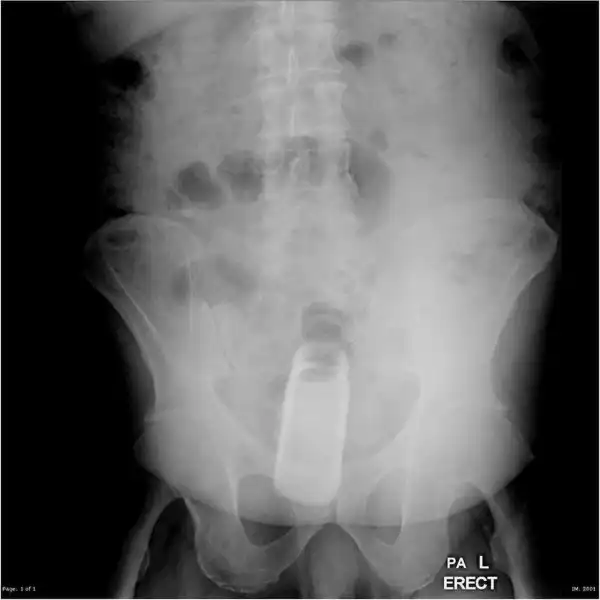

Врачебные находки в интимных местах

Или как впихнуть невпихуемое :lol:

Из личной коллекции. Извлек из очень озорного дедушки.

Самое интересное, что со слов пациентов, будучи совсем голыми поскользнулся и упал аккурат причинным местом на указанный предмет)))))

В ванной на флакончик с шампунем.

вот как на рентгене выглядит мужик со стальными яйцами и хером)))))